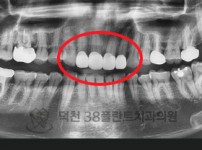

치료전후